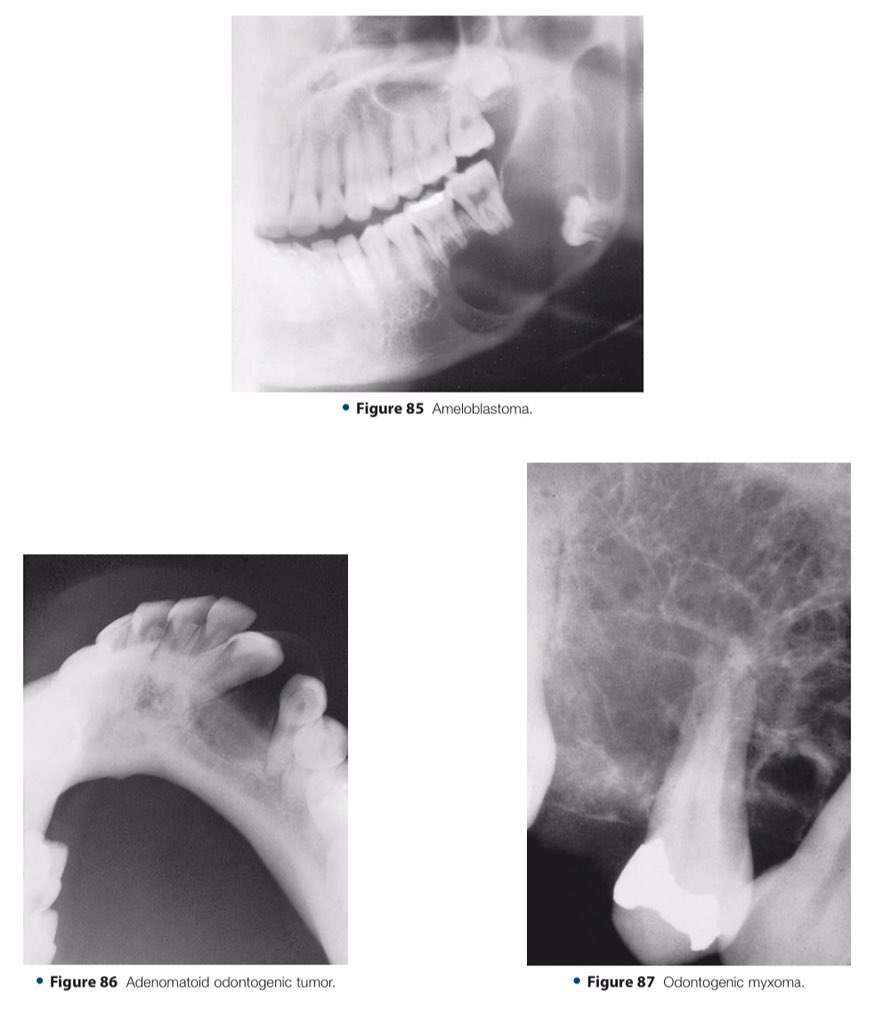

🔍| Differential Diagnosis Approach to Jaw Lesions. #aboutDent